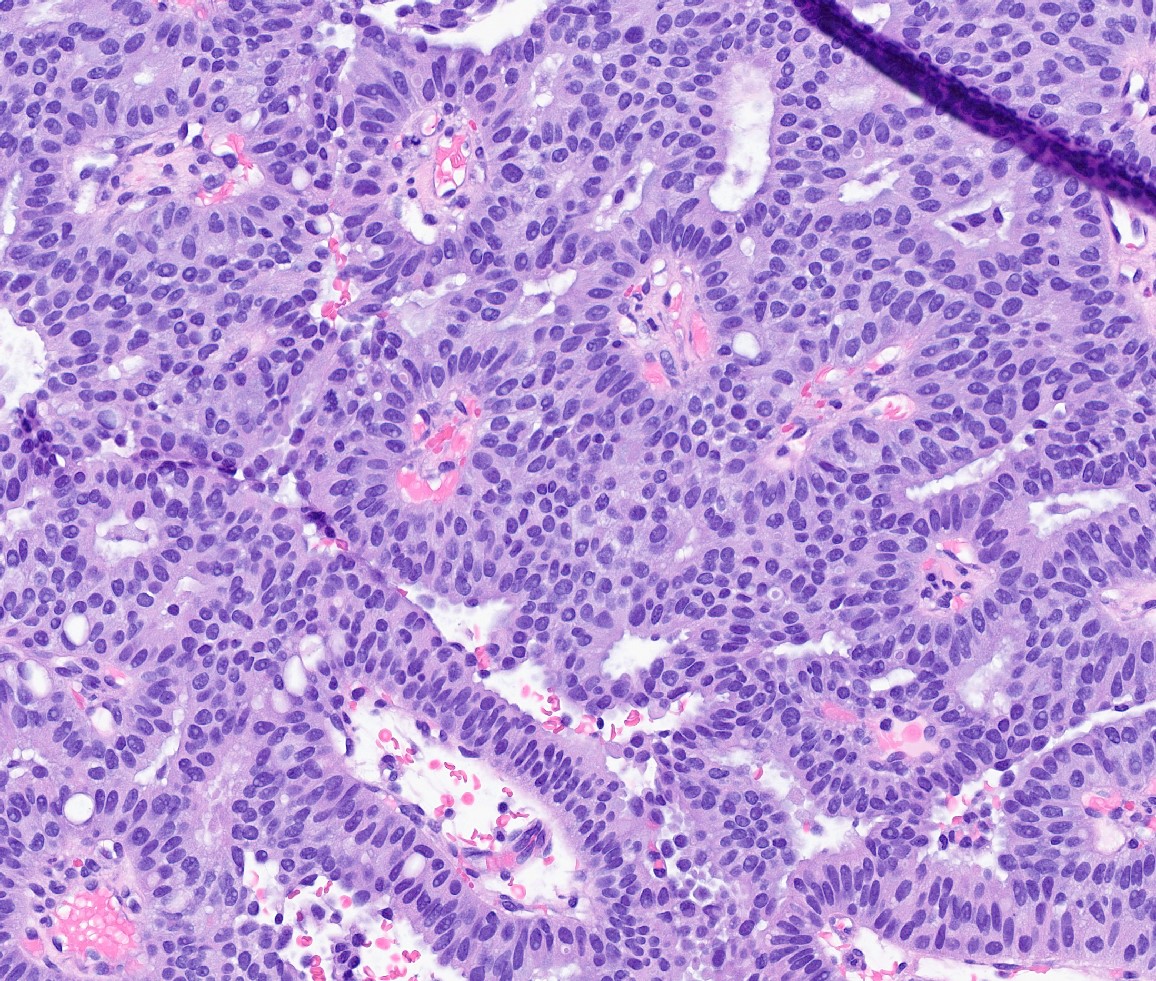

- Papillary tumor with pushing borders, may be within a cystically dilated duct, surrounded by a thick fibrous capsule (Histopathology 2008;52:20, Mod Pathol 2021;34:1044, Virchows Arch 2022;480:5)

- Delicate papillary fronds with fibrovascular cores lined by cuboidal to columnar epithelial cells with low to intermediate grade atypia

- Cribriform and solid architecture may be present

- Low mitotic activity (average 3 mitoses per 10 high power fields [HPFs]) (Am J Surg Pathol 2011;35:1)

- Most show complete lack of myoepithelial cells along the papillae and around the periphery of the tumor (Am J Surg Pathol 2006;30:1002, Am J Surg Pathol 2011;35:1)

- Basement membrane markers (collagen IV, laminin) may be expressed around the periphery (Pathobiology 2021;88:359, Am J Clin Pathol 2009;131:228)

Microscopic (histologic) images

Contributed by Kristen E. Muller, D.O. , Mariel Molina Nunez, M.D. and Julie Jorns, M.D. (Case #518)